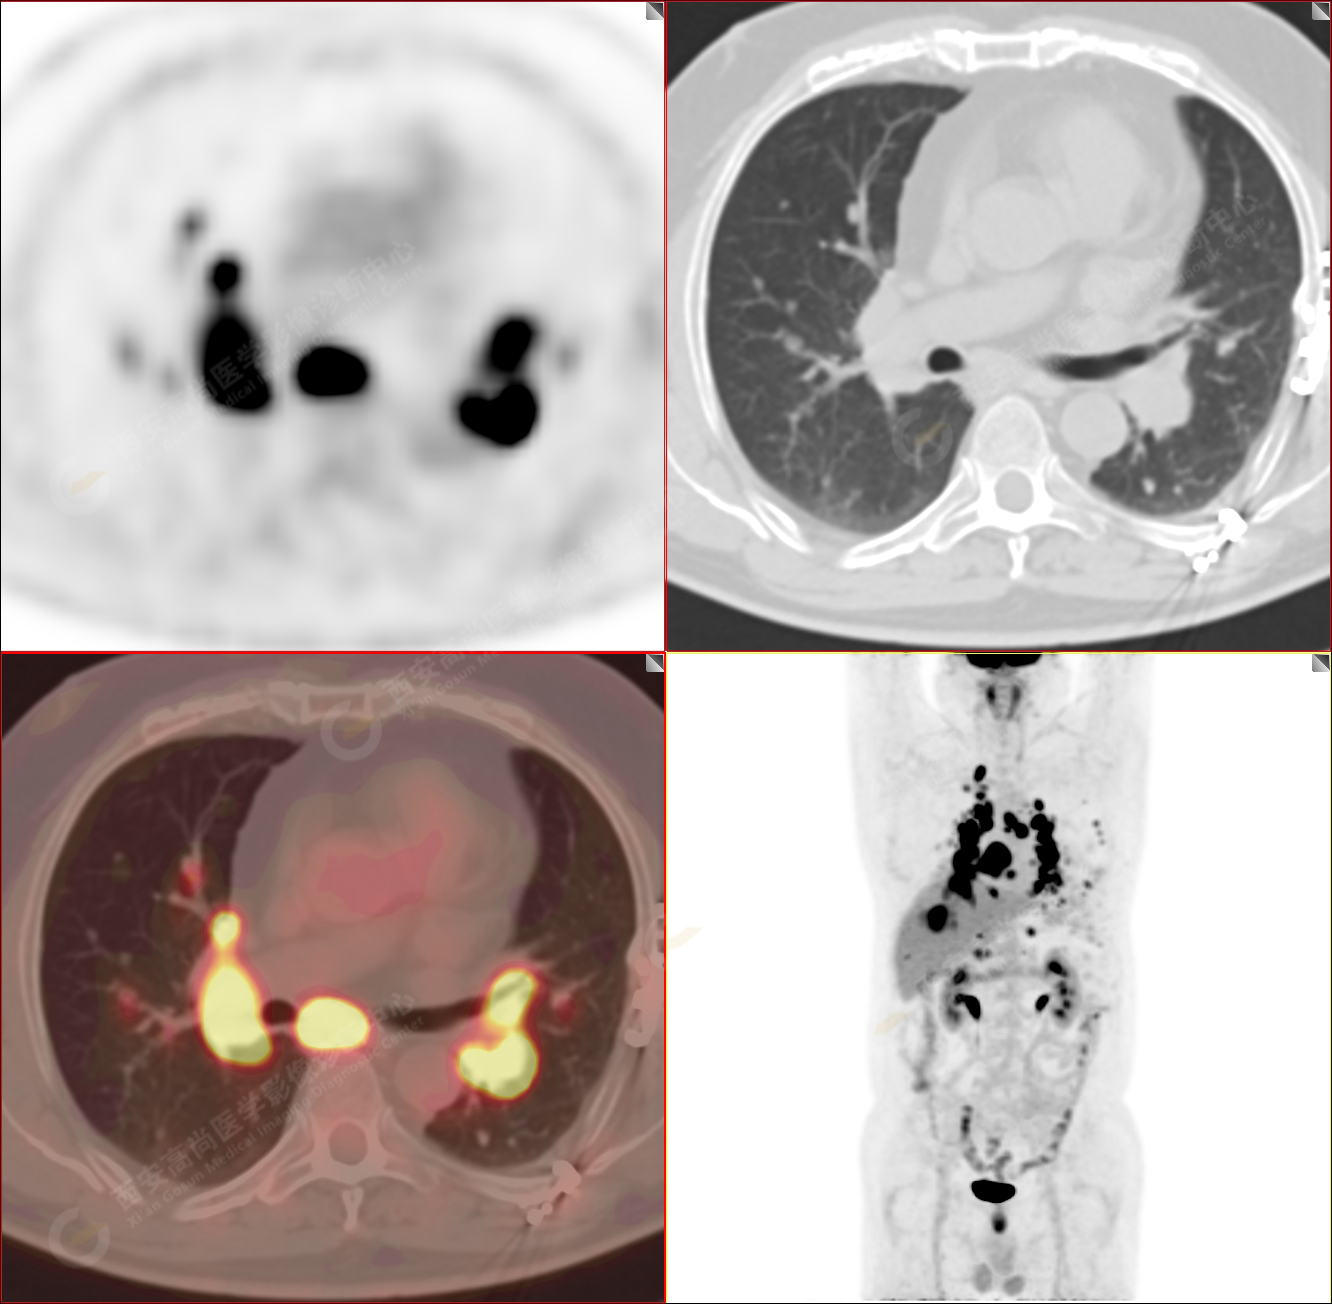

PET/CT-MR診斷結(jié)節(jié)病雙肺及全身多發(fā)淋巴結(jié)廣泛累及1例【西安高尚病例】

男性,53歲,頭暈半月入院,CT發(fā)現(xiàn)肺內(nèi)腫塊,雙肺多發(fā)大小不等實(shí)性及粟粒樣結(jié)節(jié),雙肺門(mén)及縱隔多發(fā)腫大淋巴結(jié)。病程中無(wú)發(fā)熱、胸悶氣及胸部不適。既往:左側(cè)肋骨外傷史。

PET/CT圖像